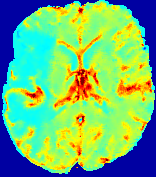

4.3.2 Diffusion Imaging via Advection-Diffusion

Slice #1Slice #2Slice #3Slice #4Slice #5Slice #6Dgtsuperscript𝐷gtD^{\text{gt}}Refer to captionRefer to captionRefer to captionRefer to captionRefer to captionRefer to captionDestsuperscript𝐷estD^{\text{est}}Refer to captionRefer to captionRefer to captionRefer to captionRefer to captionRefer to captionRefer to caption0.300.300.300.240.240.240.180.180.180.120.120.120.060.060.060.000.000.00(mm2/s)𝑚superscript𝑚2𝑠(mm^{2}/s)𝐕est𝟐subscriptnormsuperscript𝐕est2\|\bf{V}^{\text{est}}\|_{2}Refer to captionRefer to captionRefer to captionRefer to captionRefer to captionRefer to captionRefer to caption0.00300.00300.00300.00240.00240.00240.00180.00180.00180.00120.00120.00120.00060.00060.00060.00000.00000.0000(mm/s)𝑚𝑚𝑠(mm/s)

Figure 15: PIANO identifiability testing: diffusion imaging via advection-diffusion. Top row shows Dgtsuperscript𝐷gtD^{\text{gt}} used for simulating ground truth pure diffusion. Rows below show the estimated Destsuperscript𝐷estD^{\text{est}} and 𝐕est2subscriptnormsuperscript𝐕est2\|{\bf{V}}^{\text{est}}\|_{2} on corresponding slices. Note that the plotted value scale for 𝐕est2subscriptnormsuperscript𝐕est2\|{\bf{V}}^{\text{est}}\|_{2} is 0.01 of that for Dgtsuperscript𝐷gtD^{\text{gt}} and Destsuperscript𝐷estD^{\text{est}}.

Similarly, we test the behavior of PIANO when estimating both advection and diffusion from a pure diffusion-driven process. The goal is to determine if PIANO is able to recognize that there is only diffusion governing the given concentration time-series. We use the same ‘Diffusion Imaging’ data simulation of Sec. 4.2.1 as the concentration dataset, PIANO estimates both velocity 𝐕estsuperscript𝐕est{\bf{V}}^{\text{est}} and diffusivity Destsuperscript𝐷estD^{\text{est}}. Estimation results in Fig. 15 confirm PIANO’s identifiability again: the estimated 𝐕est2subscriptnormsuperscript𝐕est2\|{\bf{V}}^{\text{est}}\|_{2} is almost invisible compared to Destsuperscript𝐷estD^{\text{est}}, even plotted with a 1%percent11\% value range compared to that for Destsuperscript𝐷estD^{\text{est}}. On the other hand, Destsuperscript𝐷estD^{\text{est}} achieves comparable estimation performance as ‘Diffusion Imaging via Diffusion’ in which PIANO predicts Destsuperscript𝐷estD^{\text{est}} alone (shown in Fig. 13).